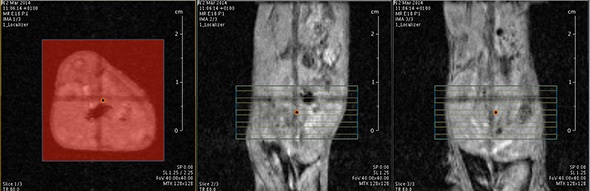

I think that also the low-field, let’s say the low/intermediate field to work at the 1 Tesla for instance as in the case of this beautiful Icon system, this gave us unique possibilities. Anytime we use a gadolinium-based agent or more in general a paramagnetic basic agent the best field is the 1 Tesla.

So, we can show that there is a real advantage of working at 1 Tesla in comparison to for instance 7 or 9 Tesla when one is using a relaxation enhancer to target a specific epitope in the region of interest.

The possibility to use complementary imaging modality was our task in the last 10 or so years. And this changed quite drastically the structure of our group, because we have to get users quickly used to the basic principles in order to have efficient imaging reporter for the other imaging modalities.